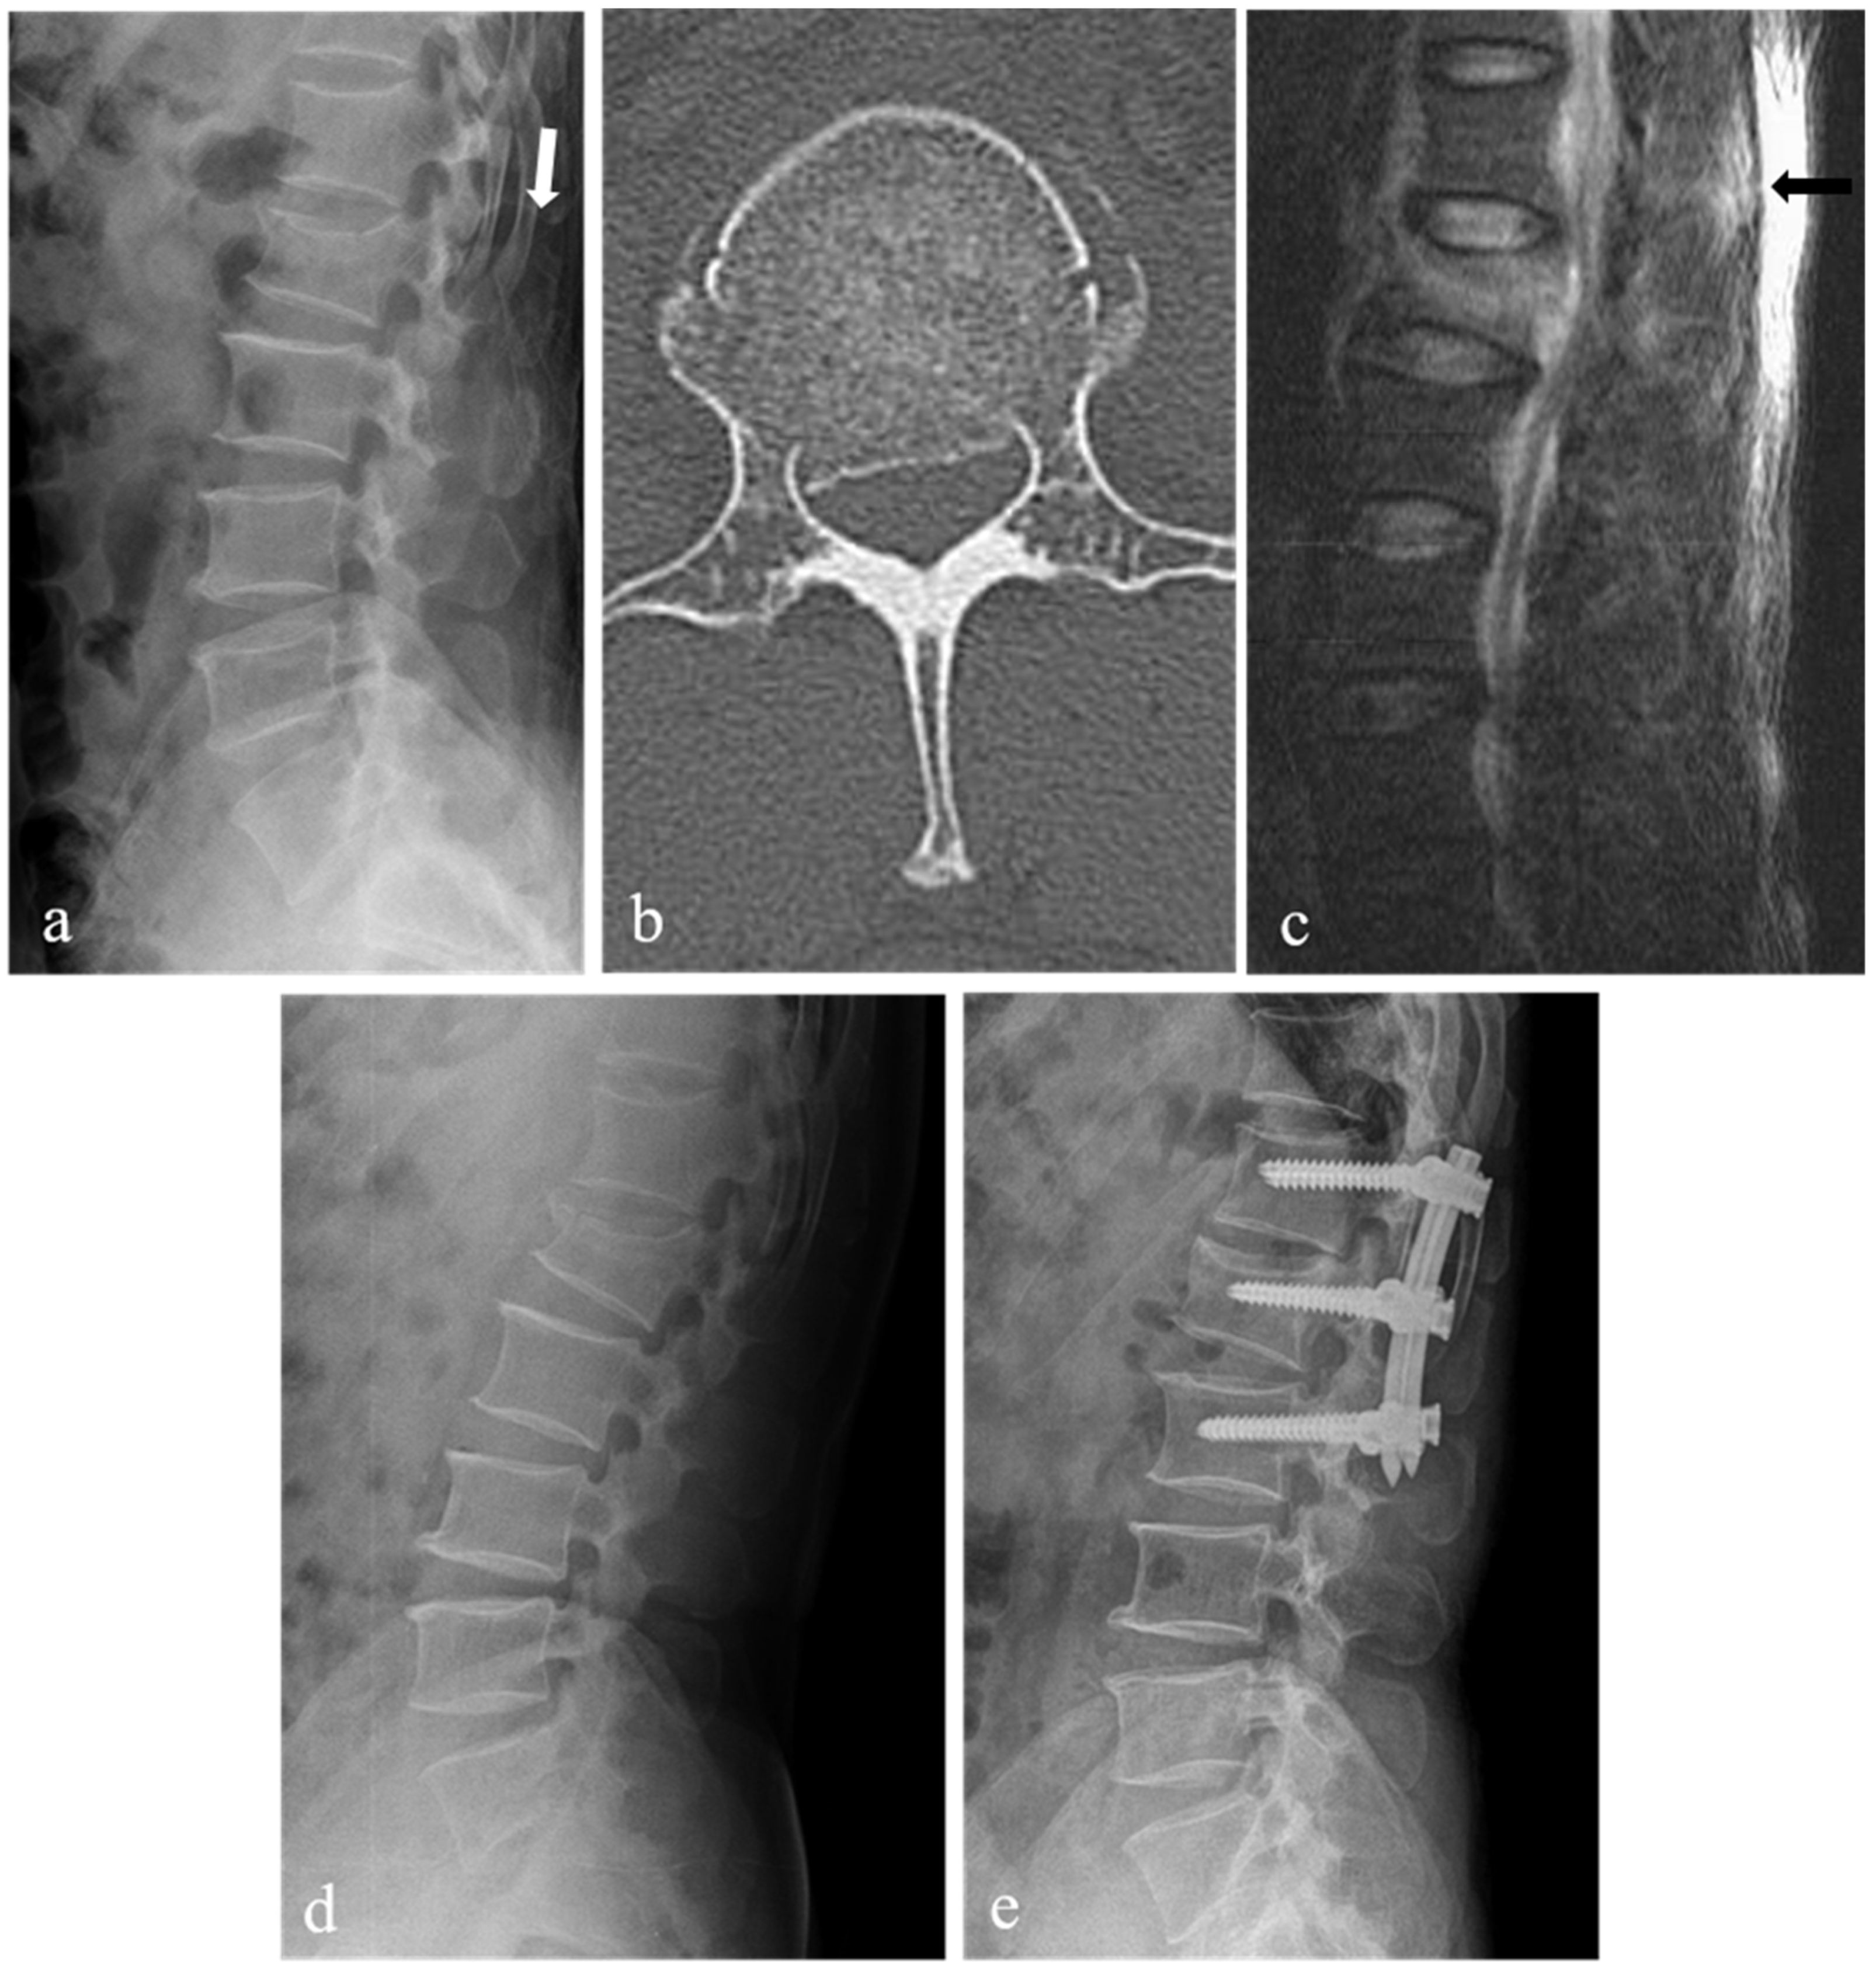

| Spinal canal compromise (%) ‡ | 27.9 ± 7.6 | 35.7 ± 13.3 | 0.03 |

| Loss of vertebral body height (%) ‡ | 28.6 ± 7.8 | 34.1 ± 6.0 | 0.01 |

| Kyphotic angle (°) ‡ | 10.1 ± 6.2 | 13.9 ± 5.0 | 0.04 |